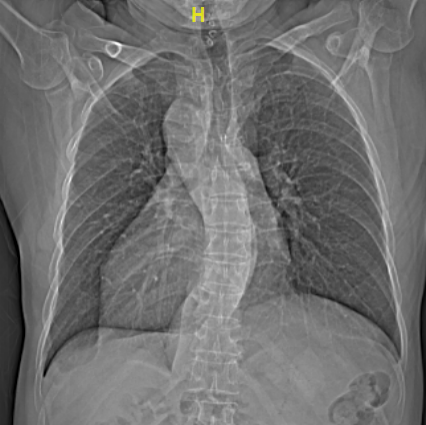

与正常人心脏位置偏左,心尖部在胸腔左侧相反,66岁的梁大叔心脏却长在了右胸腔,好像是正常心脏在镜子里的“影子”,医学上叫做“镜像右位心”。1年前,他一活动就感到心慌气喘,出现反复心悸等症状,被确诊为房颤。

进一步的心脏超声检查发现,梁大叔不仅有右位心,还有永存左上腔的先天性畸形,手术治疗又增加了不少难度。这些先天心脏畸形不仅会造成医生手术操作的不便,而且术中穿刺和导管放置稍有不慎,就可能出现穿孔、大血管损伤、心脏填塞等致命风险。面对如此棘手的手术,不少电生理团队都难以“接招”,梁大叔和家属多方打听,慕名来到华体会体育官方网站 。

不久前引进华体会体育 的亚洲首台心血管专用型CT率先上阵,对患者进行了高精度的心脏扫描,清晰显示了心腔结构、肺静脉及毗邻组织等,为手术开展提供了高质量的影像基础。术中则应用了先进的三维电解剖标测系统,在心腔内超声指导下,常栋、李强两位主任医师率队凭借扎实的手术功底,成功在非常规位置穿刺房间隔,实现了导管精准定位,消融了病灶,更在术中尽可能减少了x线的应用。短短不到三小时,长期困扰梁大叔的房颤终于顺利解除,这颗特殊的心脏也恢复了正常的节奏。